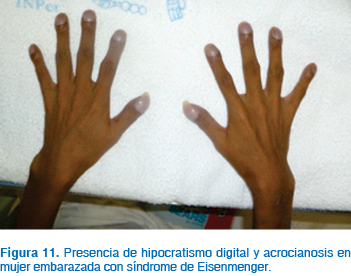

El síndrome de Eisenmenger es la complicación más crítica de las pacientes que presentan algún tipo de defecto cardiaco con cortocircuito13,18,22 (Figuras 9 a 11). Este síndrome se desarrolla a través de los años conforme se incrementa el grado y severidad de la hipertensión pulmonar cuando no existe corrección del defecto inicial. La causa más común para la aparición del síndrome es un gran defecto septal seguido de la persistencia del conducto arterioso. El mecanismo de desarrollo es el siguiente: el aumento del flujo a la circulación pulmonar en un inicio es tolerado por la vasodilatación pulmonar; sin embargo, conforme pasa el tiempo existe aumento de las resistencias vasculares pulmonares por cambios en la íntima de estos vasos, aumentando la resistencia hasta niveles severos; la dificultad para la perfusión pulmonar genera aumento de la presión en la arteria pulmonar, ventrículo derecho y aurícula derecha, generando dilatación primero y luego hipertrofia de estas cavidades. En estas circunstancias, la presión en las cavidades derechas cardiacas puede superar las presiones de las cavidades izquierdas venciendo las resistencias vasculares sistémicas e invirtiendo el flujo del cortocircuito, siendo inicialmente de izquierda a derecha para posteriormente ser de derecha a izquierda. En estas condiciones, parte del gasto cardiaco derecho pasa a la circulación izquierda sin pasar por los pulmones, generándose cianosis en la paciente.13

La disnea de esfuerzo es el síntoma de presentación más frecuente, seguido por palpitaciones, edema, fatiga, hemoptisis, síncope y cianosis progresiva, además de insuficiencia cardiaca derecha en fases avanzadas.6,13 El síndrome de Eisenmenger es una importante causa de muerte en obstetricia; en países desarrollados, la mortalidad reportada es de un 30% y ocurre con frecuencia en la resolución del embarazo, en el puerperio inmediato, sobre todo en la primera semana; sin embargo, existen publicaciones que señalan una mortalidad de 50 a 80%.10 Generalmente, los síntomas de falla cardiaca ( New York Heart Association > 2), reducción de la función ventricular izquierda, problemas cardiovasculares durante el embarazo e insuficiencia severa de la válvula pulmonar, especialmente combinada con reducción de la función ventricular derecha, están asociados con incremento en riesgo para la mujer embarazada.19

La cianosis supone un riesgo significativo para el feto, si la saturación de oxígeno es < 85%, con alta probabilidad de mortalidad perinatal.10

El embarazo en pacientes con síndrome de Eisenmenger requiere de vigilancia médica continua, con la finalidad de identificar datos de cianosis e insuficiencia cardiaca de manera temprana. La alta tasa de mortalidad se asocia con trombosis intracardiaca, por lo que está indicada la anticoagulación, especialmente en el tercer trimestre. Existe una alta incidencia de trombosis y muerte súbita en el postparto inmediato y en las primeras cuatro semanas del puerperio. El trabajo de parto espontáneo es el tipo de resolución idónea; existe un incremento significativo de la mortalidad en pacientes sometidas a operación cesárea con anestesia general, debido a que las condiciones que generan hipotensión, caída en las resistencias vasculares sistémicas, depresión miocárdica, aumentan de manera crítica la persistencia del flujo a través del defecto de las cavidades, de tal manera que la hipoxia se hace más severa y habitualmente no responde a ninguna maniobra.10